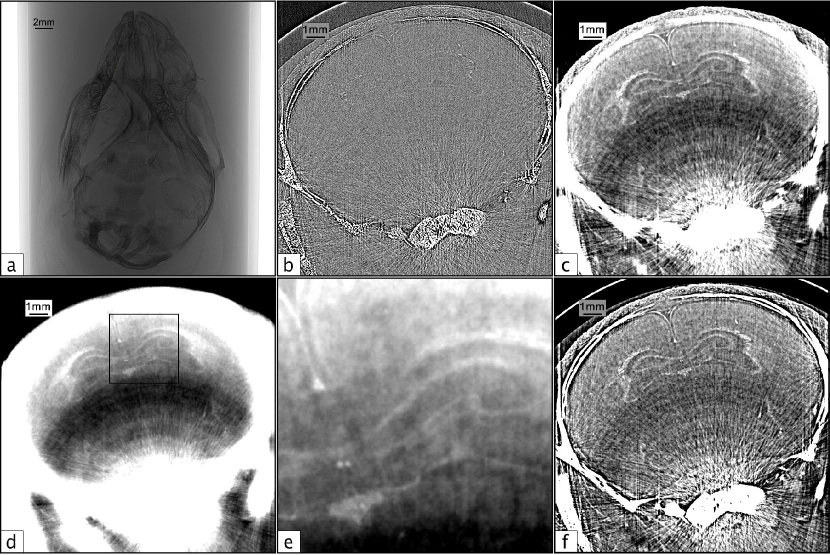

Recent studies have demonstrated that PCXI-CT is an effective tool for small animal studies of the brain, providing high resolution images of tissue structures and clear delineation between grey and white matter[15, 16, 17, 18, 19]. Beltran et al.[20, 17] showed a 200-fold increase in signal-to-noise ratio using PCXI-CT over absorption contrast, indicating that in situ PCXI-CT can lead to very large improvements over conventional absorption contrast CT. A similar example from our data collected at the SPring-8 synchrotron in Japan is shown in Fig. 1, showing the signal-to-noise ratio (SNR) and contrast-to-noise ratio (CNR) improvement that can be achieved with phase contrast and phase retrieval.

Refer to caption

Figure 1: a) A single propagation-based projection image of an excised close-to-term rabbit kitten brain, suspended in agarose. The bracket indicates the position of the brain in the tube. b) Phase contrast tomographic slice of the rabbit kitten brain in (a). Note that the visible structures can only be seen due to the phase shifts imparted by propagation and would not be visible at all in absorption contrast CT. c) Phase-retrieved tomogram of the brain from (a) and (b). CTs were acquired at 24 keV with an object-to-detector distance of 5 m. See methods section for experimental details.

For materials of similar composition (and hence refractive index), such as the grey and white matter of the brain, the single-material phase retrieval algorithm applied with respect to the tissue/air interface works quite well to resolve the boundaries between these materials. Structures that are unresolved or poorly resolved with attenuation contrast alone become visible upon phase retrieval, since the phase retrieval filter suppresses noise, thereby increasing the SNR and CNR. Ideally, phase retrieval performed with respect to the grey/white matter boundary provides the best contrast resolution of brain structures, however when imaging the brain in situ, the inaccurate phase retrieval at the bone/tissue interface causes excessive blurring that overwhelms the features within the soft tissue of the brain. Fig. 3 shows the in situ analogue to Fig. 1. In panel 3c, phase retrieval has been performed with respect to bone/air interface, resulting in an over-blurring at both the grey/white matter and bone/tissue boundaries. Nevertheless, the brain structure is more clearly resolved in Fig. 3c than in Fig. 3b, despite the incorrect phase retrieval at the bone/tissue interface and the associated artefacts caused by the the highly attenuating bone. In panel 3d, phase retrieval has been performed with respect to the tissue/air interface, again resulting in a highly-blurred reconstruction. In this case, brain features are very well resolved (panel 3e) but are dominated by the bone artefacts.

Figure 3: Panels (a) - (c) are the in situ analogue to the panels in Fig. 1(a) - 1(c) for a full head of a dead close-to-term rabbit kitten, though the region of the brain is not the same as Fig. 1. CTs were acquired at 24 keV with a propagation distance of 5 m. a) A single propagation-based projection image of a whole rabbit kitten head suspended in agarose. b) Phase contrast tomogram of the rabbit kitten head in (a). c) Phase retrieved tomogram of the head from (a) and (b) created using the single-material algorithm with respect to a bone/air interface. d) Phase retrieved tomogram using the single-material algorithm with respect to a tissue/air interface. e) A close-up of the square region outlined in (d). f) Phase retrieved tomogram using the two-material algorithm (equation (15)) with respect to the bone/tissue interface.

When phase retrieval is performed with respect to the bone/tissue interface using equation (15) (Δδ/Δμ=(δ2δ1)/(μ2μ1)=5.66×1010Δ𝛿Δ𝜇subscript𝛿2subscript𝛿1subscript𝜇2subscript𝜇15.66superscript1010\Delta\delta/\Delta\mu=(\delta_{2}-\delta_{1})/(\mu_{2}-\mu_{1})=5.66\times 10^{-10}), both interfaces are better resolved with a more consistent resolution across the image than with the single-material algorithm (δ/μ=1.54×109𝛿𝜇1.54superscript109\delta/\mu=1.54\times 10^{-9} and δ/μ=8.60×109𝛿𝜇8.60superscript109\delta/\mu=8.60\times 10^{-9} for bone and brain tissue, respectively). These results are shown in panel 3f, where it can be seen that the artefacts due to the highly absorbing bone are largely abated. The remaining artefacts fall into two types - ring artefacts and streak artefacts - and are ones which should ideally be corrected for prior to the phase-retrieval step. Streak artefacts across high-contrast edges are caused by multiple factors, and determining the dominant contributing factors is important for improving the SNR and CNR for in situ brain imaging.